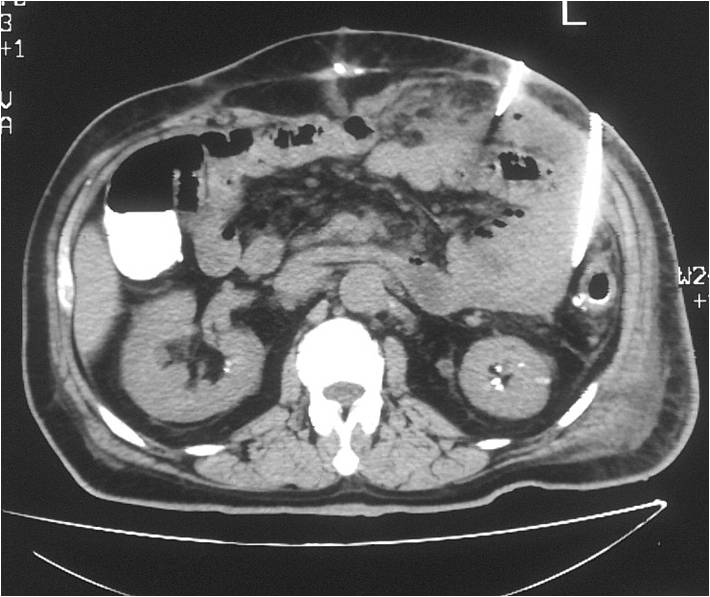

- Placement of two sump catheters in a abdominal abscess (surgery of inflammatory bowel disease), displacement of upper one